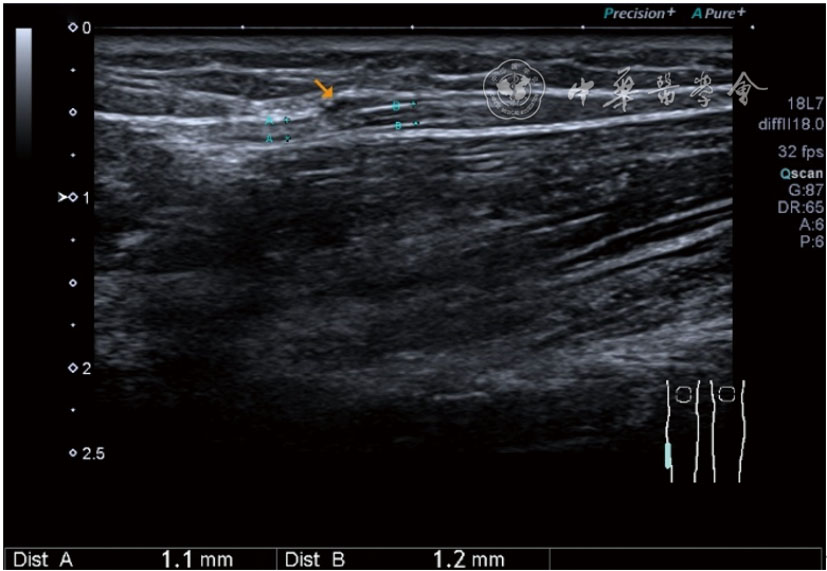

Ultrasonic diagnosis and treatment of knee musculoskeletal pain